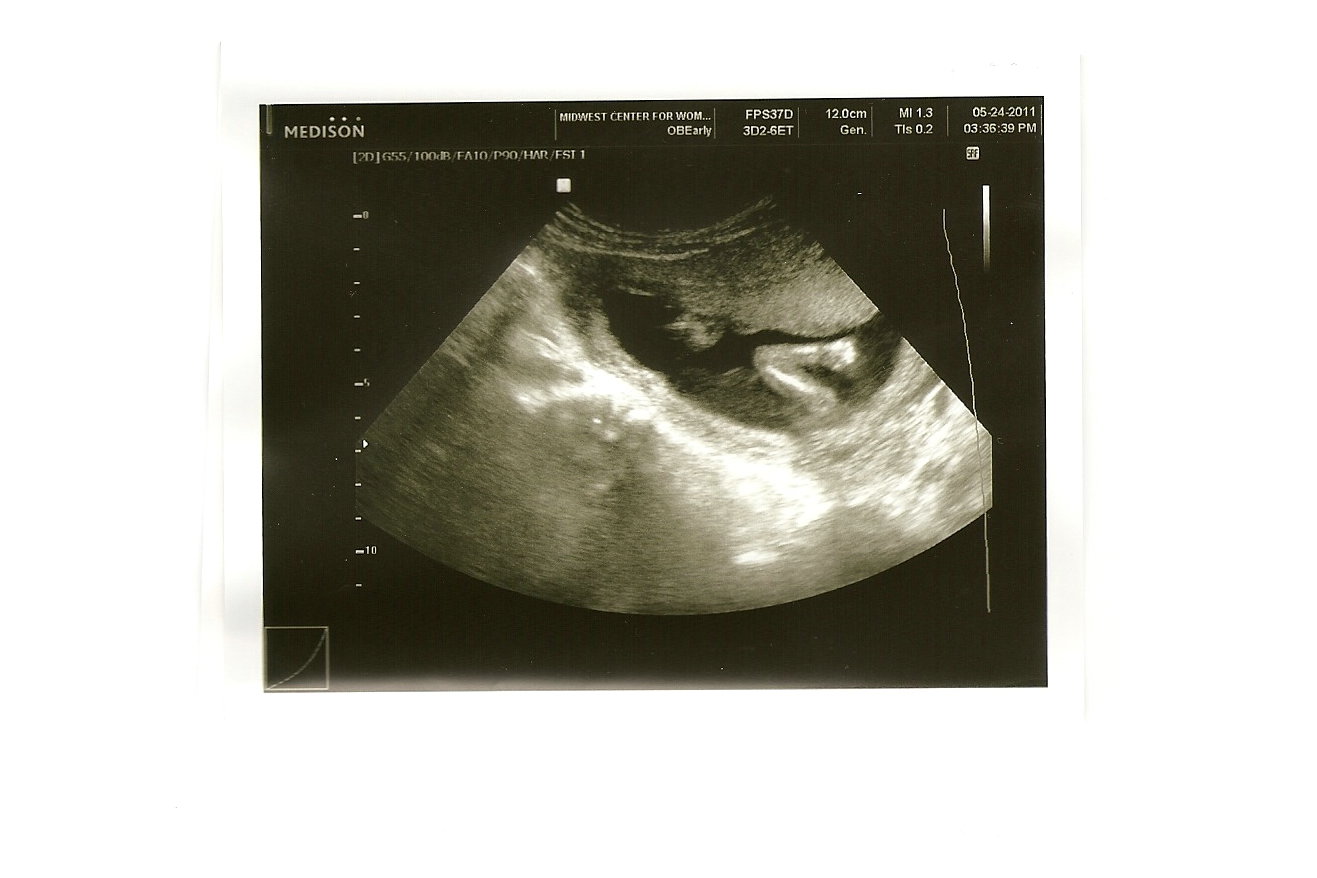

Who in their right mind would say no to that?! So I did get to see him (we still think it's a boy) and it was such a blast!!

Here you can see his spine and profile

And here you can see him trying to kick and stretch out those legs, I think he looks a little claustrophobic in there:

Here are his little legs, or I should say long legs with big feet (he's taking after his momma) stretching out, with ankles crossed:

And here is one of my favorites, simply his little arm, with his hand balled into a fist: